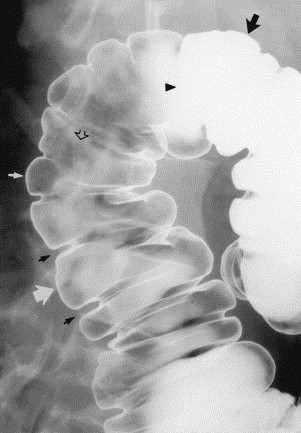

Hình 2. Hình cản quang kép, chụp khu trú cho thấy bề mặt niêm mạc nhẵn bình thường màu xám (mũi tên rỗng). Bờ trong của lòng đại tràng nổi rõ trong vùng đọng baryt (mũi tên đen lớn), hoặc là đường trắng mỏng giữa khí và chất cản quang (mũi tên trắng nhỏ). Lưu ý, cột baryt đặc làm mờ bề mặt niêm mạc ở hướng thẳng (đầu mũi tên). Đại tràng có các chỗ phồng căng hình túi (mũi tên trắng lớn) nằm giữa các chỗ thắt – ngấn ngang (các mũi tên đen nhỏ).